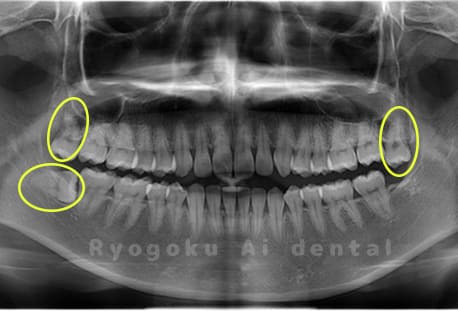

Case02

- 原因

- 下顎の水平埋伏智歯

- 治療内容

- 下顎の水平埋伏智歯を抜歯

<リスク・副作用>

手術後は痛み、腫れ、痺れなどの副作用が生じる場合があります。